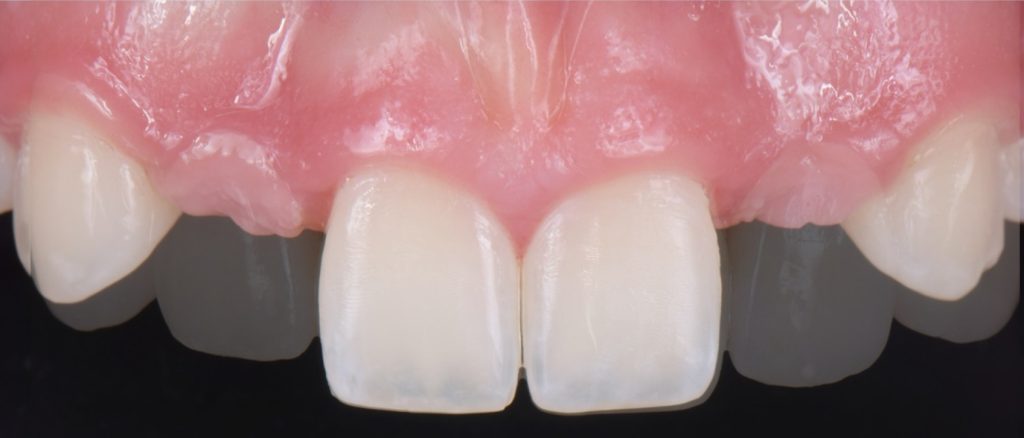

Solution #1: Canine Substitution for Missing Lateral Incisors

Canine substitution is the least invasive option and a popular alternative, but it often poses esthetic and functional challenges that need to be considered and cleared (Fig. 1). From an esthetic standpoint, the canine’s shape and shade must be considered. From a contour standpoint, the width of the canine should be evaluated because they are generally larger than lateral incisors.

However, the most critical aspect to manage is the CEJ width because it cannot be narrowed. The wider the tooth at the CEJ, the more difficult it is to make a canine look like a lateral incisor. Moreover, canines typically present with a very distinctive root eminence, and if it is particularly accentuated, it could become yet another esthetic challenge — one commensurate with the patient’s lip mobility.

There is no major esthetic concern for patients where a low lip line conceals the gingival outline. Still, if there is high lip mobility and the gingival outline is not concealed, such an eminence could represent an unacceptable esthetic problem.

From a shade standpoint, canines usually are the teeth with the most saturated chroma in the maxillary arch, which often creates an esthetic challenge where this oversaturation is evident.

Consequently, considering these aspects, the ideal clinical scenario for canine substitution would be in patients with smaller shaped canines that are not oversaturated with chroma and in patients who display low lip mobility.